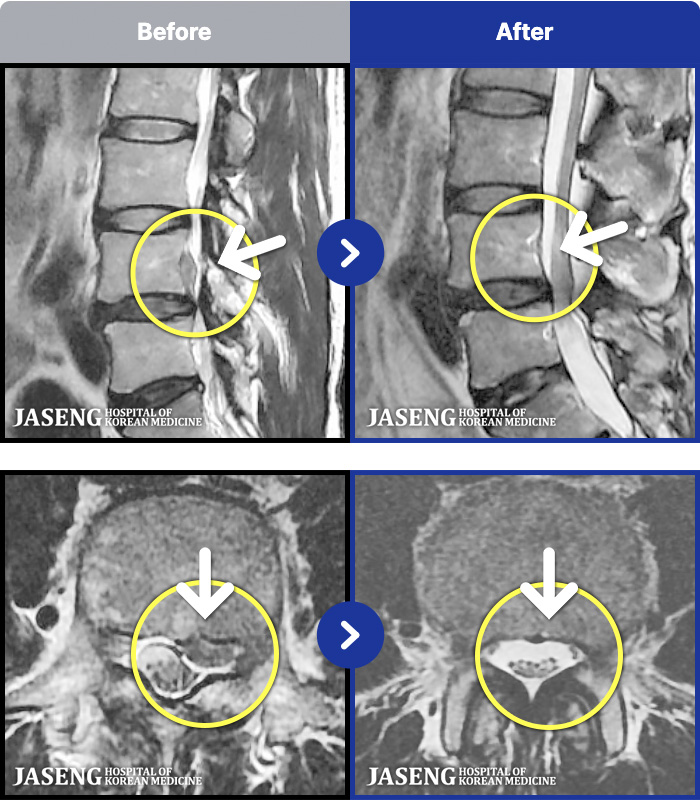

1,286 MRI ũ ʸ Ȯϼ.